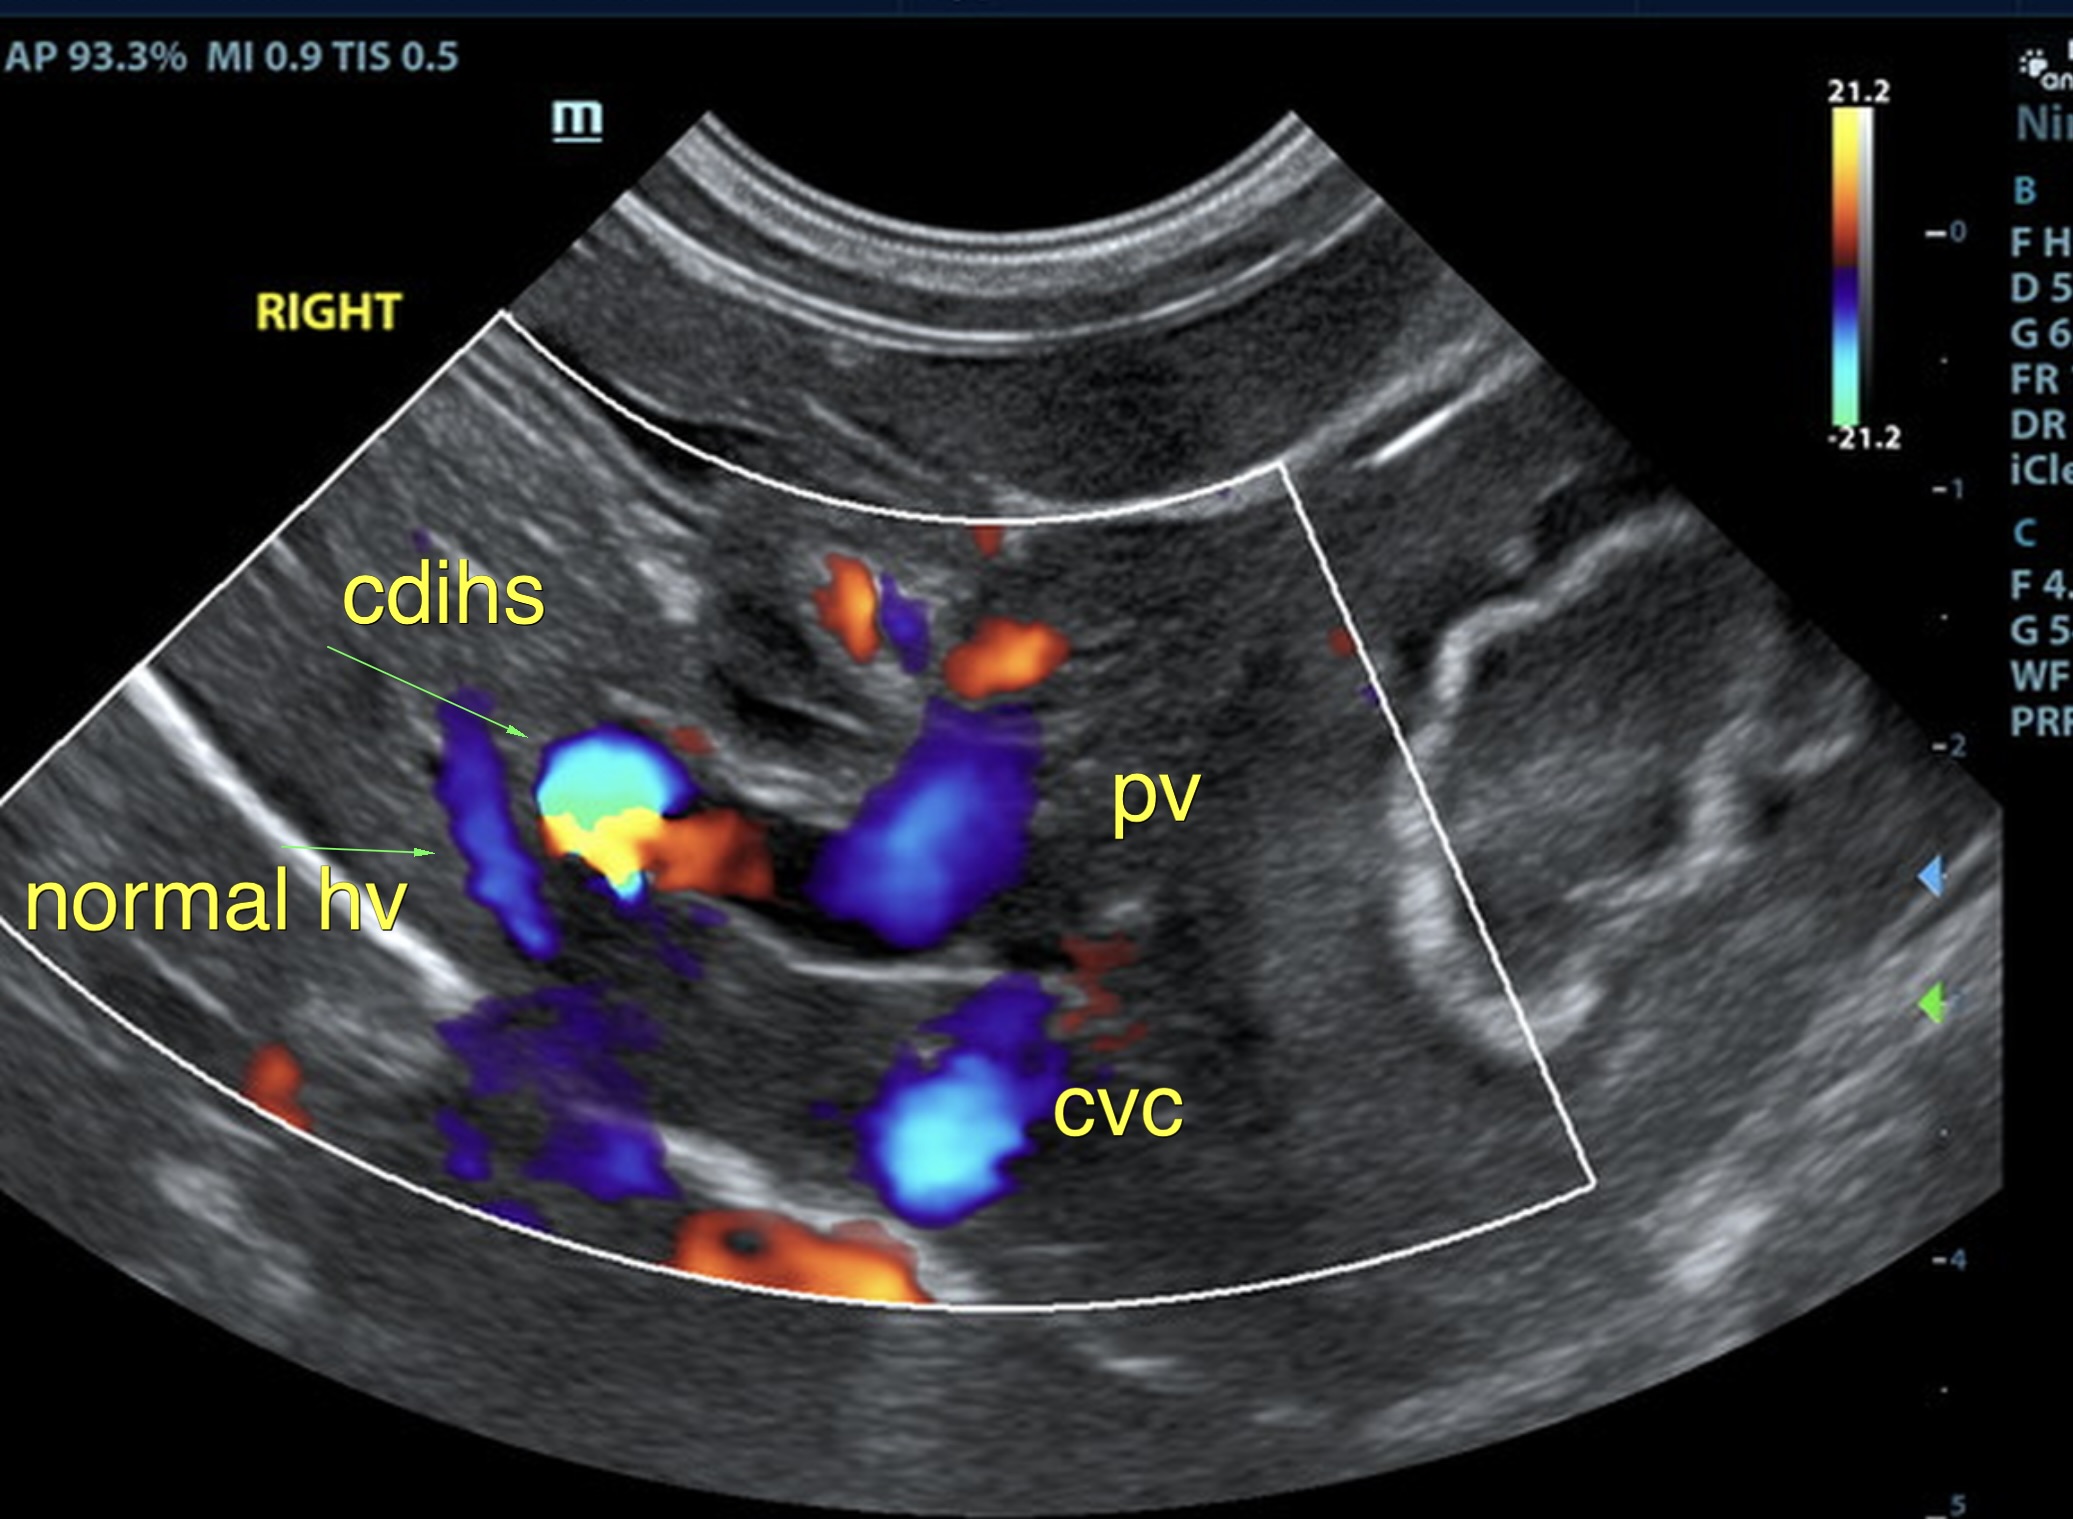

The liver was subnormal in size, yet the portal vein and vena cava ratio was 1:1. The portal veins were subnormal in size and measured 0.34 cm. The vena cava was enlarged and measured 0.34 cm. The vena cava was enlarged and measured 0.72 cm, aorta measured 0.4 cm. The branching of the portal vein appeared to be normal and of adequate volume. The portal vein and vena cava measured 0.5 cm each in the extrahepatic space. The splenic vein entry into the portal vein and gastroduodenal vein entry into the portal vein appear to be normal. There was one turbulent vessel in the region of the central branch of the portal vein, which may represent an intrahepatic shunt, but this could not be confirmed. The width of the shunt is approximately 0.76 cm. This is in position of central divisional shunt; however, right divisional origin cannot be completely ruled out. The gallbladder presented acceptably thin walls with primarily anechoic content. The cystic and common bile ducts were normal.